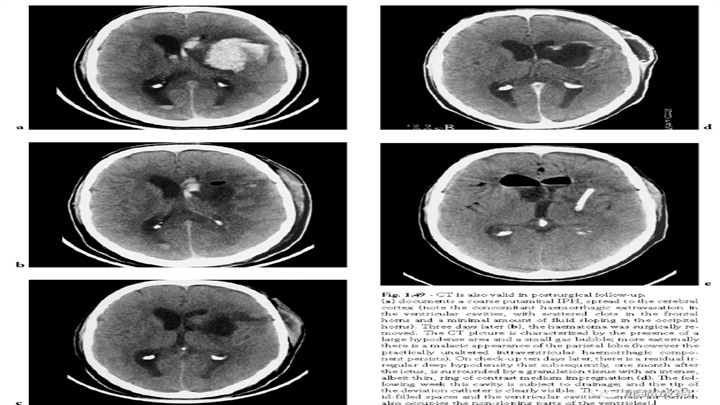

CT在手术后随访中也有效。a图示左侧壳核血肿,体积大,累及皮层、侧脑室,b图示3d后手术切除了血肿,术区见大片低密度区和小气泡,脑室内出血成分未改变。c图示10d天后存在残留的不规则的深部低密度区,d图示一个月后CT增强扫描示病变被明显强化的薄环样肉芽组织所包围。e图示接下来的一周引流术后,腔被排空,导管尖端清晰可见,脑室内可见积气。